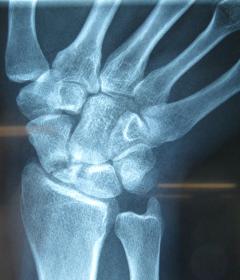

Η ψευδάρθρωση καταγμάτων του σκαφοειδούς δεν είναι σπάνια επιπλοκή (βλ αντίστοιχο κεφάλαιο). Λόγω ανατομικών και φυσιολογικών ιδιαιτεροτήτων του σκαφοειδούς ή λόγω υποτίμησης των ενοχλημάτων εκ μέρους του αρρώστου, το κάταγμα συχνά διαφεύγει της αρχικής διαγνώσεως. Αυτό οδηγεί σε ανεπαρκή αντιμετώπιση, η οποία καταλήγει σε μη πώρωση (ψευδάρθρωση) του σκαφοειδούς. Η κατάσταση αυτή αρχικά έχει ελαφρά ή καθόλου συμπτώματα, με την πάροδο όμως των ετών εγκαθίσταται προοδευτικά επώδυνος περιορισμός της κινητικότητας του καρπού και ελάττωση της δύναμης δραγμού (αδύναμο σφίξιμο σε γροθιά).

Οσο κοντύτερα προς τον αγκώνα είναι το κάταγμα (κατάγματα του κεντρικού πόλου) τόσο μεγαλύτερη είναι η πιθανότητα να εμφανισθεί και νέκρωση του κεντρικού πόλου λόγω διακοπής της αιμάτωσης (άσηπτη νέκρωση). Αυτό καθιστά ακόμη πιο δύσκολη τον χειρισμό της ψευδάρθρωσης.

Προεγχειρητικά

Περίπτωση 2: Προεγχειρητικά